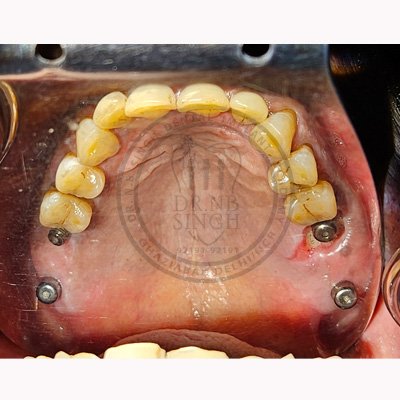

Case – 11 Baleram